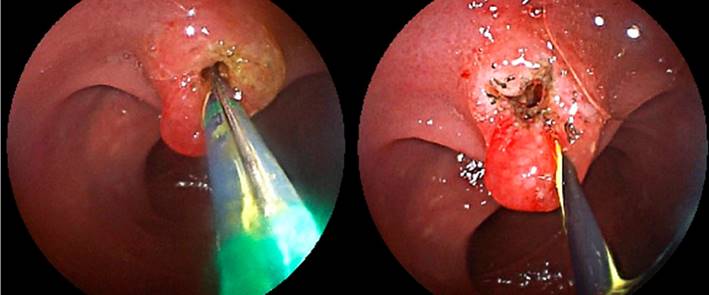

Se ingresa por el asa biliopancreática (con ayuda de la fluoroscopia) hasta el muñón duodenal (aproximadamente 150 centímetros de longitud) (Figura 3). Se identifica la papila duodenal de aspecto normal (en el cuadrante superior) (Figura 4). Se intenta la canulación con catéter punta cónica, con papilótomo de arco y con papilótomo de aguja, pero no es posible avanzar la guía hacia la vía biliar, por lo que se utiliza un papilótomo invertido; se logra avanzar la guía hidrofílica hacia la vía biliar (Figura 5).

Figura 5 Canulación con papilótomo invertido y avance de la guía hacia la vía biliar. Fuente: archivo de los autores.